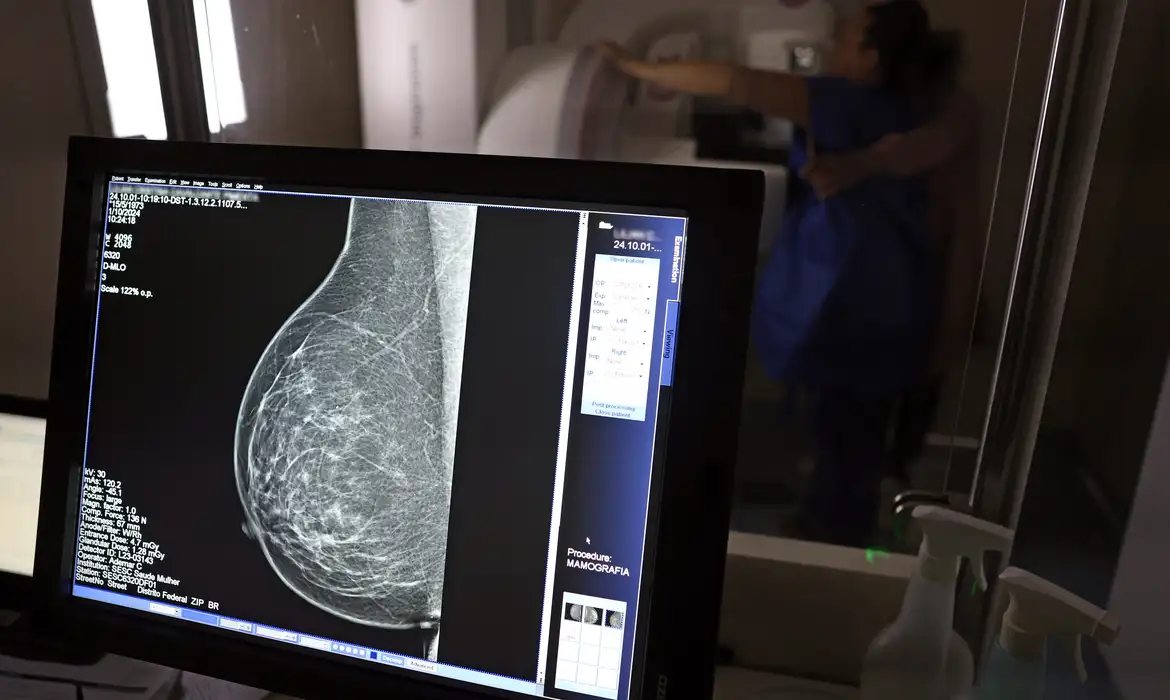

No mês de conscientização sobre o câncer de mama, um relatório destaca a importância de acesso igualitário ao rastreamento e tratamento da doença. Segundo o Atlas da Radiologia no Brasil, do Colégio Brasileiro de Radiologia e Diagnóstico por Imagem (CBR), o acesso aos mamógrafos ainda é um desafio.

O país tem 6.826 equipamentos registrados, sendo 96% em funcionamento. Metade deles está disponível no Sistema Único de Saúde (SUS), responsável por atender 75% da população. Isso equivale a 2,13 mamógrafos por 100 mil habitantes dependentes do SUS.

Na saúde suplementar, que cobre 25% da população, o cenário é mais favorável: 6,54 aparelhos por 100 mil beneficiárias, quase o triplo da rede pública. O Acre exemplifica essa disparidade — são 35,38 mamógrafos por 100 mil habitantes na rede privada, contra 0,84 no SUS.

Há disparidades regionais. Roraima tem a menor proporção (1,53 por 100 mil), seguida do Ceará (2,23) e Pará (2,25). A Paraíba lidera o ranking (4,32), à frente do Distrito Federal (4,26) e do Rio de Janeiro (3,93).

Segundo a coordenadora da Comissão Nacional de Mamografia do CBR, Ivie Braga de Paula, todos os estados têm número suficiente de aparelhos para o exame. Mas um conjunto de gargalos dificultam o acesso e geram subutilização.

“Há problemas de informação, de comunicação, de acesso e logística, principalmente na Região Norte. Por exemplo, os mamógrafos ficam nas cidades mais centrais e a população ribeirinha não consegue chegar. Às vezes, tem que andar seis a sete horas de barco para fazer uma mamografia. Até nos grandes centros, as pacientes da periferia não têm informação suficiente e enfrentamdificuldades para marcar e chegar em um local com mamógrafo”, diz Ivie.

O Brasil tem uma cobertura muito baixa de mamografias: 24%. O ideal recomendado pela Organização Mundial da Saúde é de 70%. Mesmo em lugares como o estado de São Paulo, que tem a maior concentração de mamógrafos do país, a taxa gira em torno de 26%.

Em setembro, o Ministério da Saúde ampliou as diretrizes de rastreamento, recomendando que mulheres entre 40 e 49 anos realizem mamografias, mesmo sem sintomas. De acordo com o Instituto Nacional do Câncer (Imca), mais de 73 mil mulheres recebem o diagnóstico de câncer de mama anualmente no Brasil.

“O que é efetivo na redução da mortalidade é você descobrir o tumor antes de ter sintoma clínico. Quanto menor o tumor, melhor para a gente descobrir o tratamento e maior a chance de cura. E a gente só consegue fazer isso com exames de imagem", diz Ivie.

Ela explica que no caso de diagnóstico de um câncer de mama com menos de 1 cm, a chance de cura é de 95% em cinco anos, independentemente se ele é do tipo mais agressivo. "E esses tumores só vão ser detectados na mamografia. Essas pessoas que têm que ir fazer mamografia são mulheres saudáveis. Não são mulheres doentes”, acrescenta.